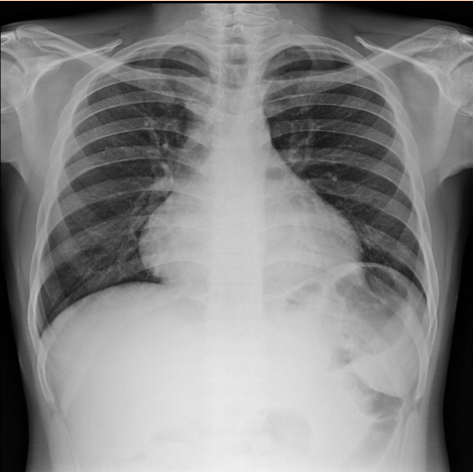

Other than ECGs which investigations can you perform on a patient with pericarditis?